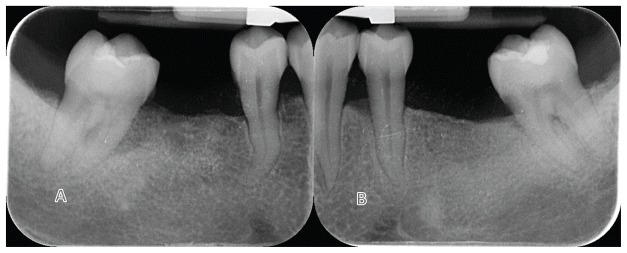

In the test group, Osstem KS BA implants (4.0 mm diameter, 15° internal taper connection, Osstem Implant) were placed. In the control group, Osstem TSIII BA implants (4.5 mm diameter, conventional 11° internal connection, Osstem Implant) were used (Figure 1). All patients underwent radiographic examination (periodical radiograph with paralleling technique) and professional oral hygiene treatment before surgery.

All surgeries were performed under local anesthesia with articaine hydrochloride and adrenaline 1:100,000 (Orabloc, Pierrel, Milan, Italy). After crestal incision and full-thickness flap elevation, implant sites were prepared either freehand or with the aid of a surgical guide. Manufacturer’s recommended protocols were followed (Osstem Implant). Bone quality was assessed subjectively. The first site was randomly assigned to receive either the KS (test) or TSIII (control) implants (Osstem Implant). Implants were placed at the crestal level or up to 2 mm subcrestally, based on anatomical conditions. Healing abutments were immediately connected if primary stability was ≥30–35 Ncm. On the contrary, cover screw would be place and second stage surgery planned. Flaps were closed with Vicryl 4.0 (or equivalent). Baseline periapical radiographs were taken with paralleling technique, for each study implant to prevent the risk of systematic error in performing periapical radiographs. Two to three months post-placement, either digital or conventional impressions were taken. Within one month, monolithic zirconia crowns bonded to titanium links were delivered after testing implant stability. Occlusal contacts were adjusted for light contact with the opposing dentition. Clinical photographs and radiographs were taken. Oral hygiene instructions were reinforced. Patients were enrolled in a maintenance program with six-month intervals. At each visit, professional oral hygiene sessions and clinical evaluations were performed, with particular attention to implant stability and occlusion. In addition, periapical radiographs were taken annually. According to the study protocol, patients were followed for research purposes for up to 5 years. Radiographs of both treatments are reported in figures 2–5. At each center, a single experienced clinician performed all surgical and prosthetic procedures, with optional assistance from a second clinician (e.g., a prosthodontist). All interventions and follow-ups were conducted at the respective sites using standardized materials and protocols to ensure consistency.